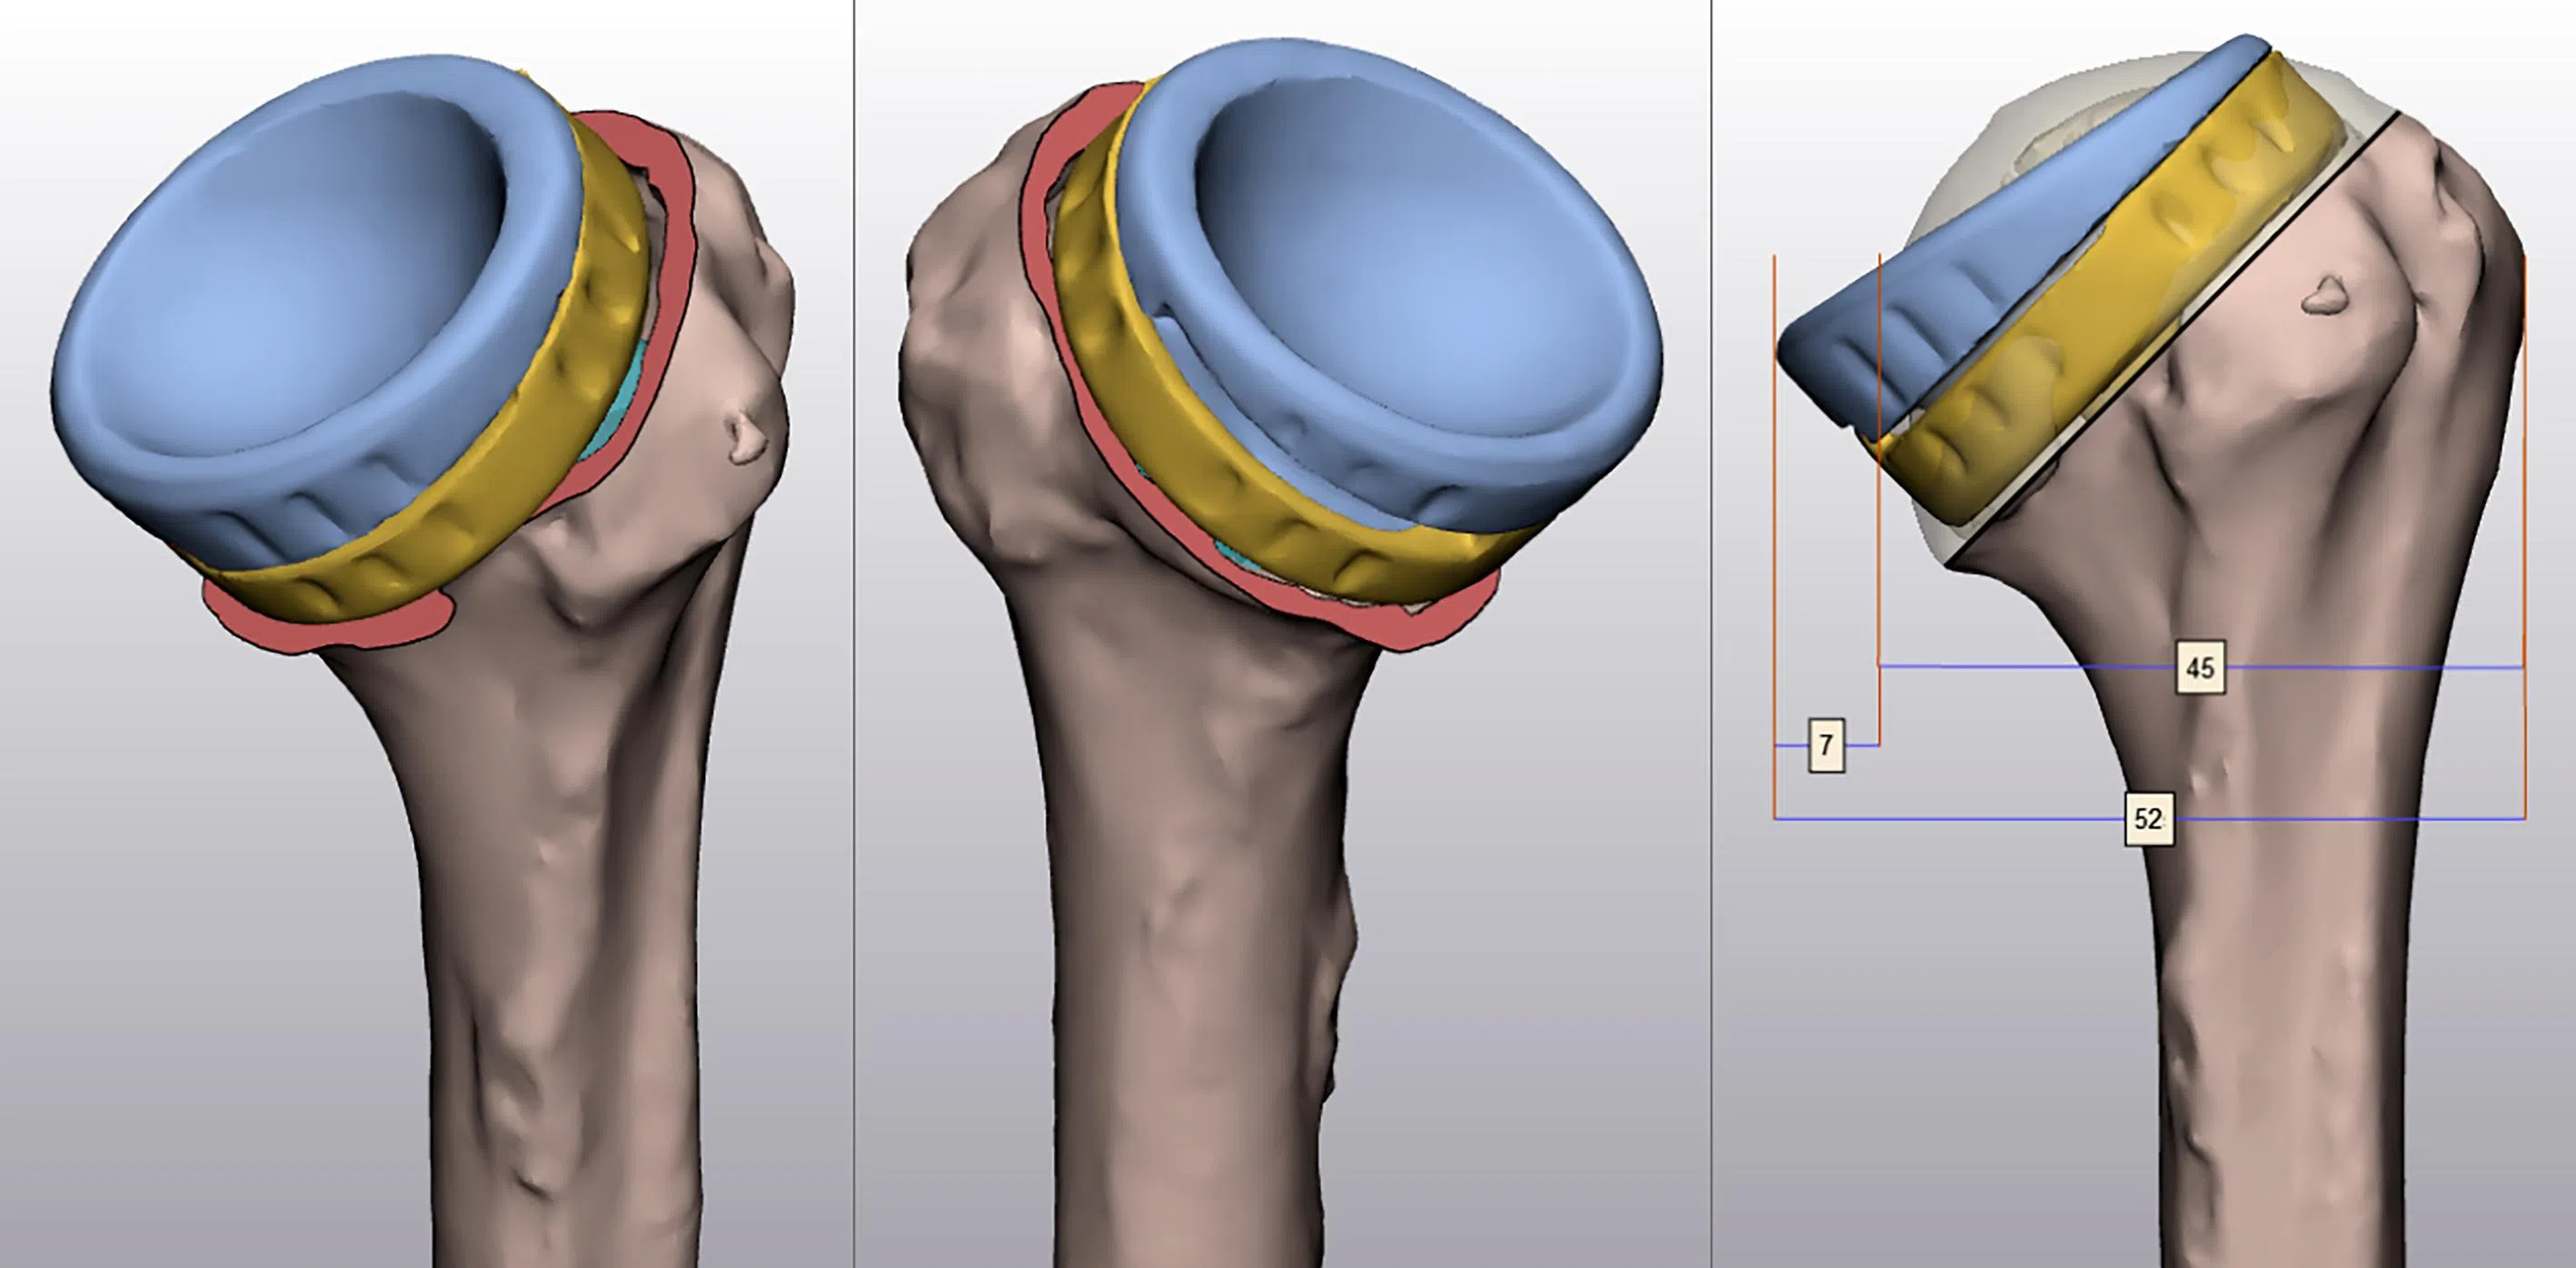

2. A surgeon and a biomechanical engineer create precise digital models. This is to optimise implant positioning and sizing by using virtual surgical planning – a technology-driven, 3D-simulation process to plan and rehearse the procedure.

3. The virtual surgical planning of the humerus implant used in shoulder replacements results in higher accuracy, and reduces surgical time and complications.

Software tools are used for finite element analysis, and computational modelling is used to simulate biomechanical behaviour under various conditions. The different colours show varying levels of loading on the shoulder.